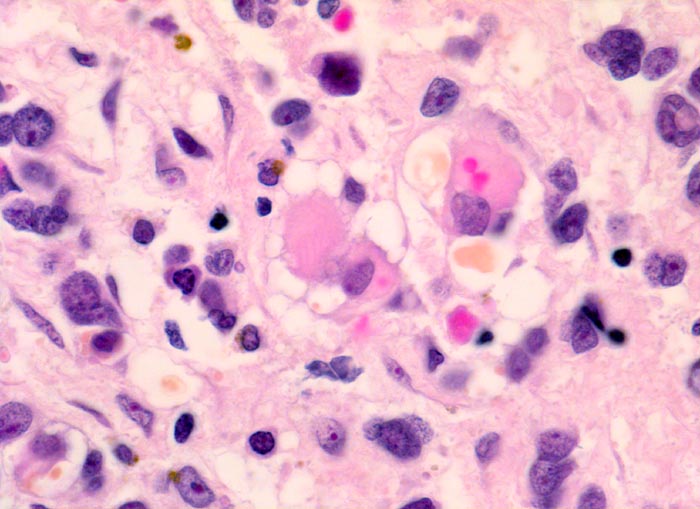

embryonales Rhabdomyosarkom

Neben primitiven ovalen und spindeligen Zellen mit sehr wenig Zytoplasma sind in der Bildmitte Rhabdomyoblasten mit vakuolisiertem Zytoplasma erkennbar. Dabei handelt es sich um sogenannte Spinnwebenzellen. Die Vakuolen entstehen durch herausgelöstes Glykogen.

Schmerzloser rasch wachsender Tumor im oberen inneren Quadranten der Orbita mit Verdrängung des Bulbus nach temporal. Diplopie.

Histologie

630